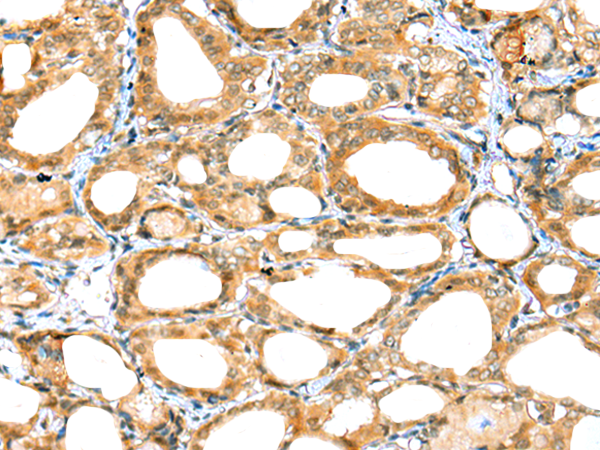

分类: 科研抗体货号: P01960别名: UAP; UBAP; NAG20; UBAP-1应用: IHC反应种属: Human, Mouse, Rat